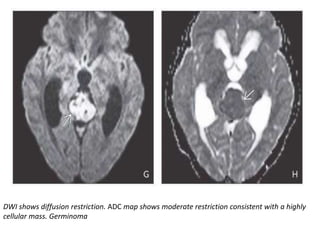

DWI shows diffusion restriction. ADC map shows moderate restriction consistent with a highly

cellular mass. Germinoma